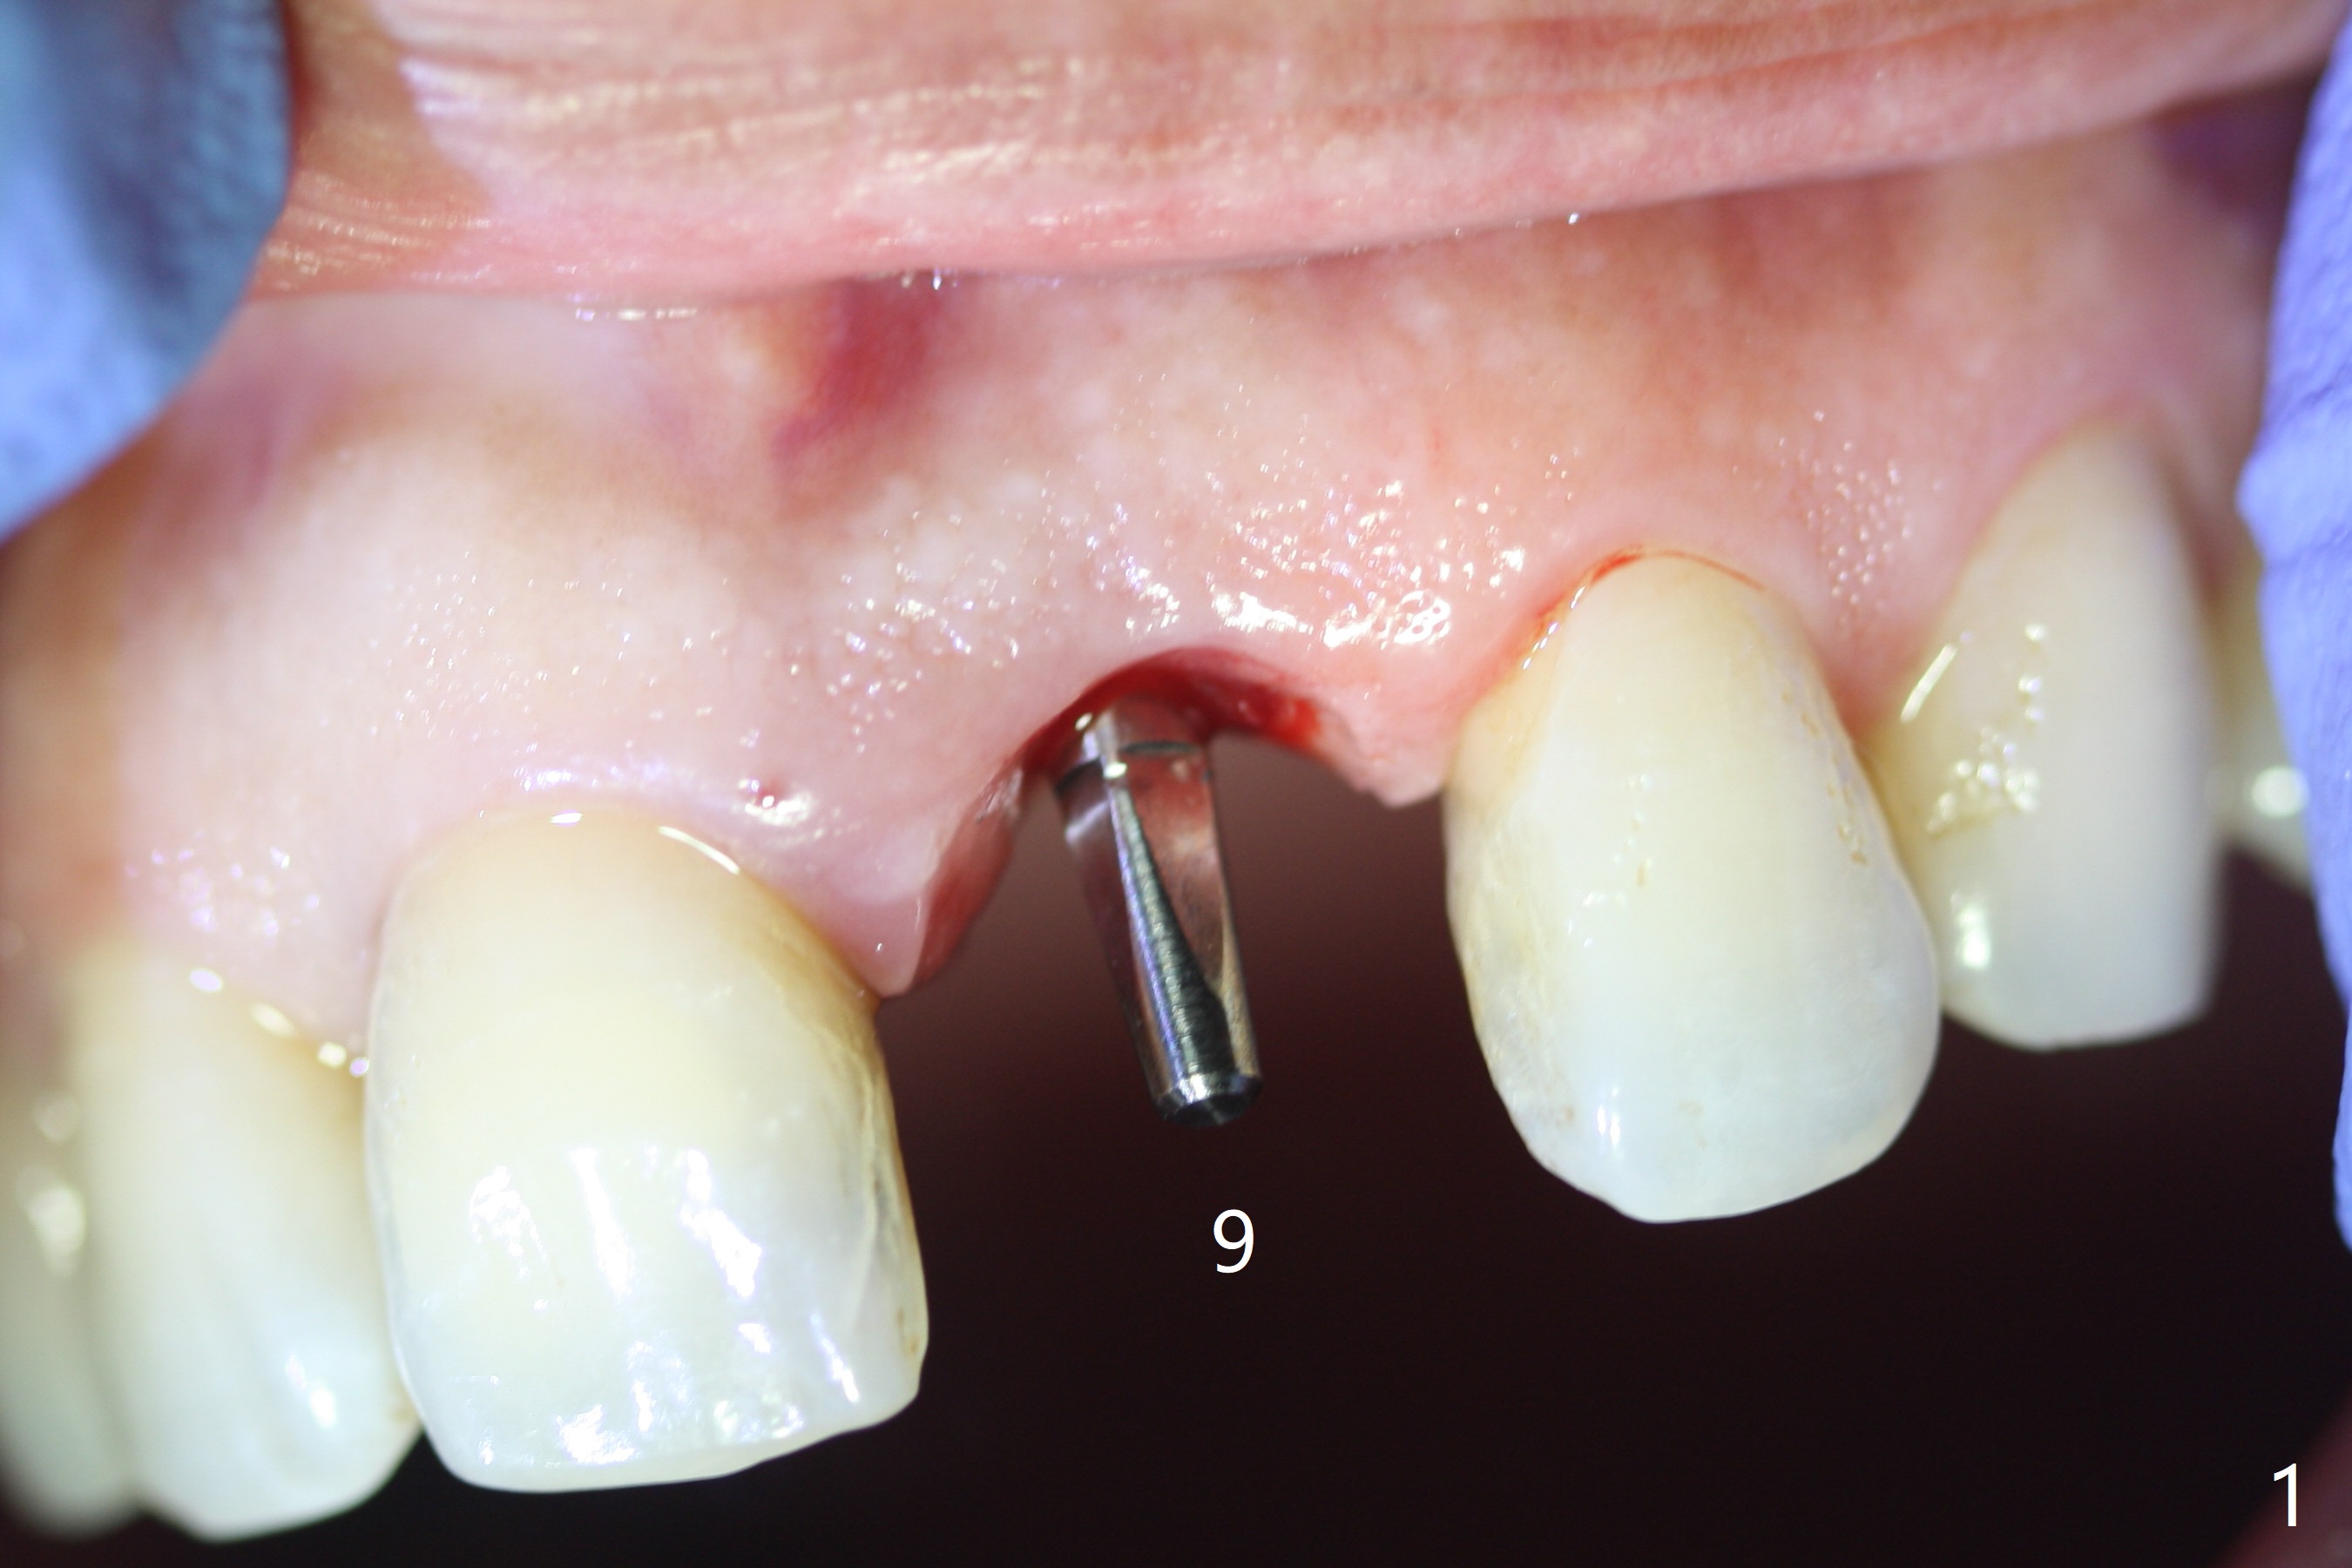

Except the depth, a 2.5x10 mm mini implant is placed with precision (in trajectory) at #9 (Fig.1-5). Confidence using surgical guide for the narrow ridge is enhanced due to placement of two digits against the buccal and palatal plates for tactile sensation. The depth issue is related to overprep with 2.2 mm drills. The torque is <15 Ncm. The immediate provisional is bonded to the neighboring teeth for retention. It appears that smaller drills should be made for guided surgery (such as 1.5 and 2.0 mm). The immediate provisional looks acceptable buccal and occlusal 3 weeks postop (Fig.6,7), although the palatal gingiva is erythematous (Fig.8, which is common after use of drill for access (tissue laceration), OHI offered). Three months postop (Fig.9), the palatal gingiva looks healthy (data not shown), while there is no bone loss around the implant (Fig.10). It remains the same 5 months postop (immediately post cementation, Fig.11) and 3,11 months post cementation (Fig.12,13). The labial gingiva is healthy (Fig.14), while the palatal one is less erythematous and edematous (Fig.15) than earlier (Fig.8).